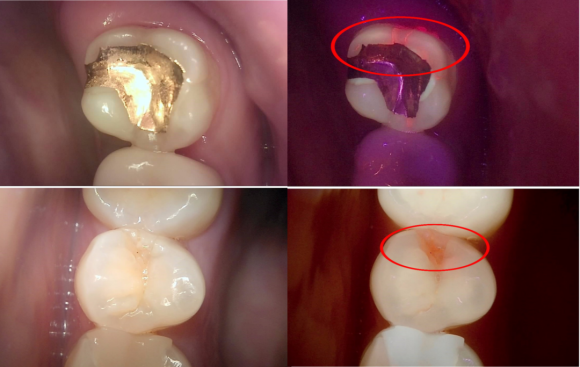

증상과 상태에 따라 큐레이, 치근단 X-ray, CT 등을 적절히 활용하여 문제의 원인을 다양한 방법으로 확인하는걸 원칙으로 있습니다.

큐레이 촬영 사진